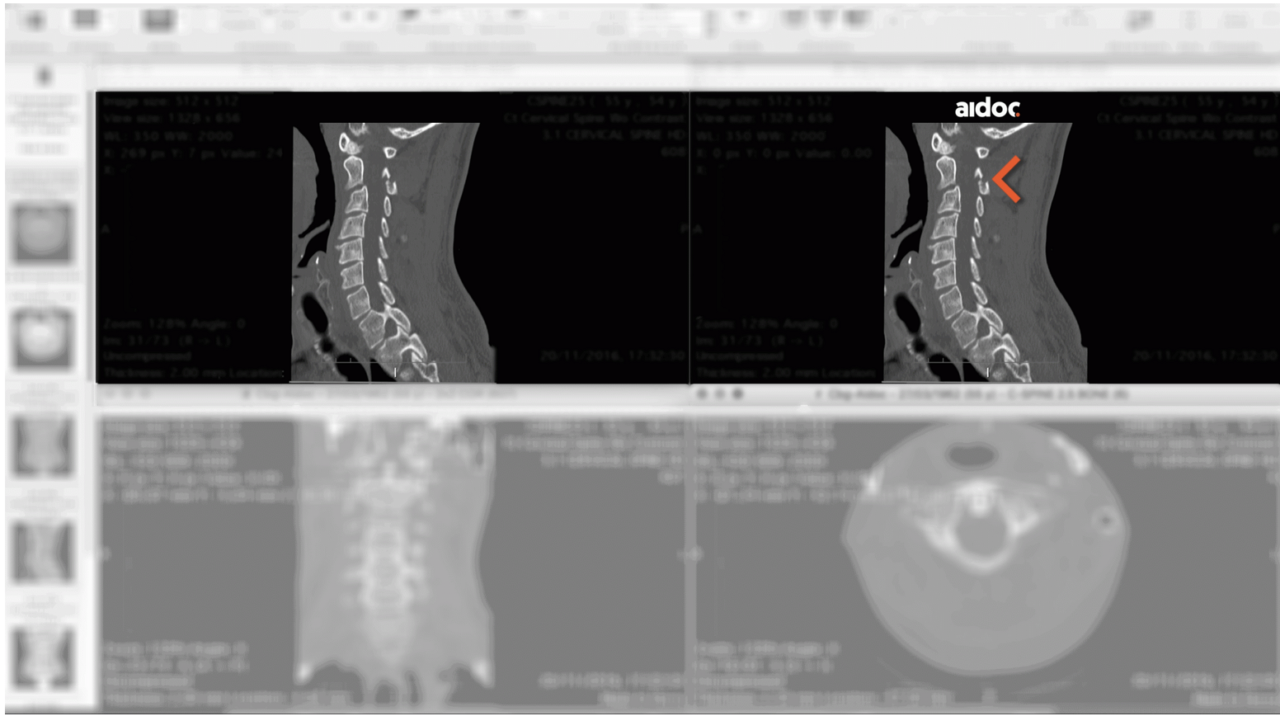

Una novedosa tecnologia israelí logra marcar las anomalías agudas para ayudar a los radiólogos en la clasificación del flujo de trabajo. Esto significa de forma contundente mejorar la calidad de la atención.

Aidoc resuelve este problema proporcionando a los radiólogos soluciones avanzadas para aumentar la eficiencia y agilizar la atención al paciente dentro de su entorno de trabajo existente.

La solución de Aidoc analiza imágenes médicas directamente después de que el paciente es escaneado y notifica al radiólogo con los casos y hallazgos sospechosos para ayudar a priorizar los casos sensibles y potencialmente mortales a tiempo.